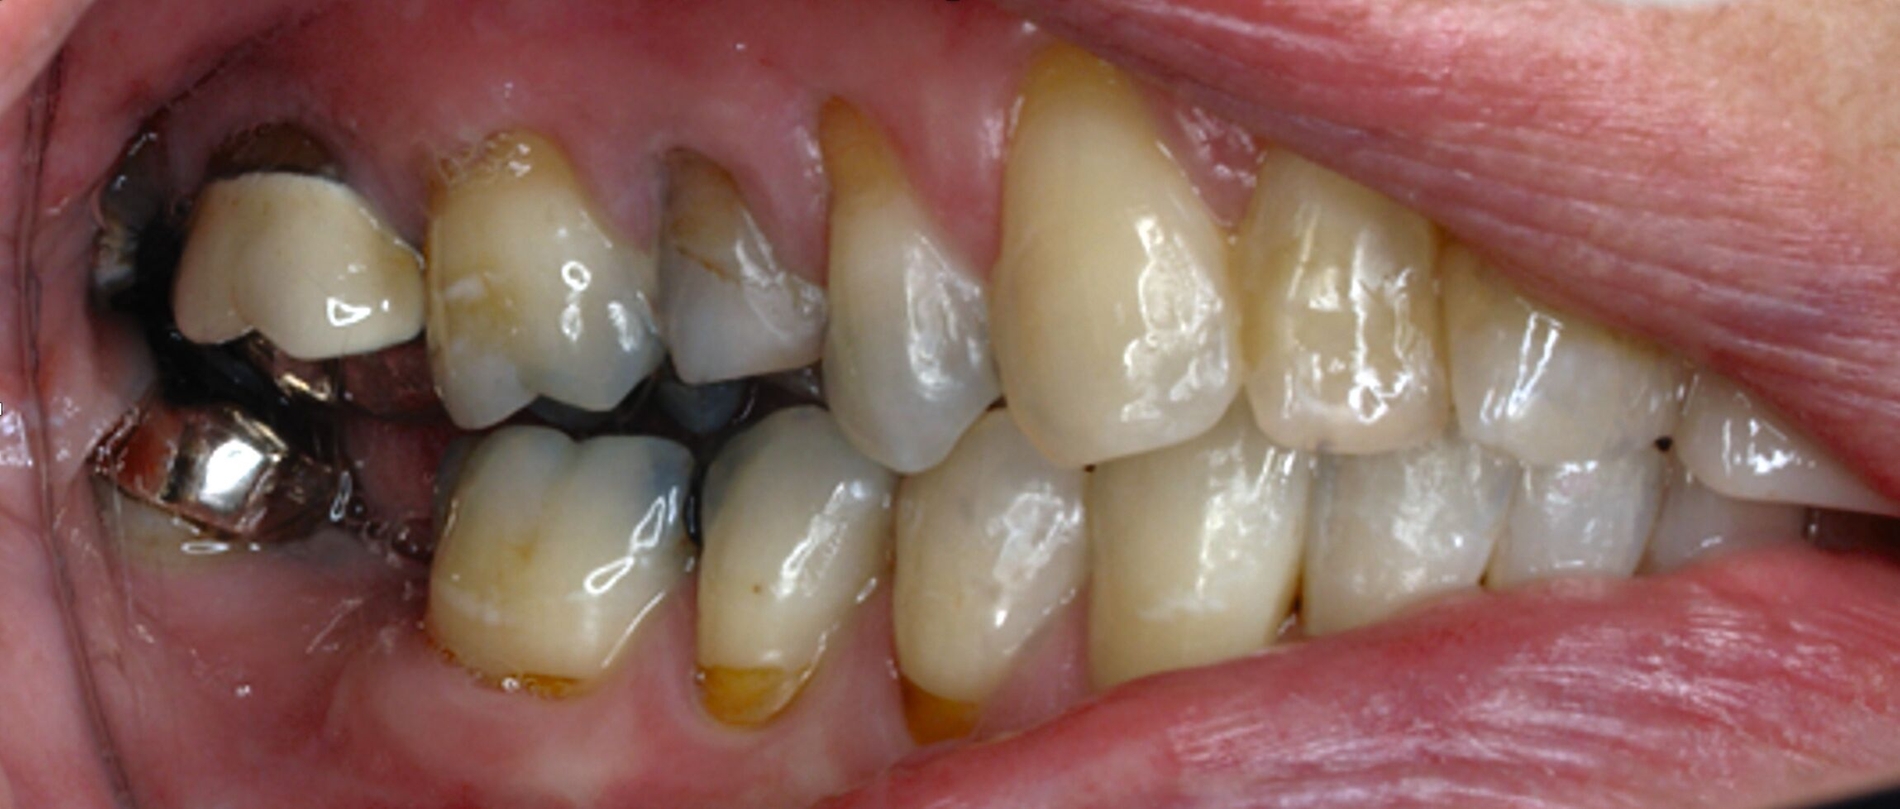

Klinisch zeigten sich diverse großflächig, mehrheitlich mit Amalgam gefüllte Seitenzähne, suffiziente endodontische Behandlungen an den Zähnen 16 und 14 sowie intakte Kronen an den Zähnen 16 und 48 (Abbildung 2). Ein Parodontaler Screening-Index (PSI) wurde erhoben (1-1-0-0-2-1), der stabile Verhältnisse nachwies. Das funktionelle CMD-Screening zeigte eine nicht-druckdolente Kaumuskulatur sowie eine uneingeschränkte Mundöffnung ohne Reiben und Knacken.

Tabelle 1 zeigt das entsprechende Befundschema mit den Taschentiefen mesial und distal, den Lockerungsgraden und den Sensibilitätsüberprüfungen mittels Kältespray (ViPr). Die Ruheschwebelage wurde mithilfe des Zielinsky-Zirkels auf 2 mm bestimmt. Die Nonokklusion im Seitenzahnbereich konnte auf circa 1,5 mm bemessen werden. Tabelle 2 spiegelt das entsprechende Okklusionsprotokoll wider. Das Okklusionsprofil wird auch in den Abbildungen 3a bis 3c deutlich.